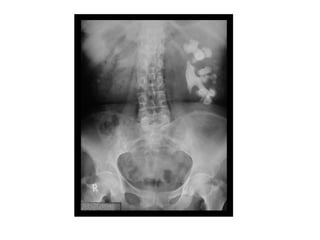

Technical Aspects

• Check that it is

standard supine AP

I. Bones: Ribs, Lumbosacral spine, Pelvis, Upper femur

II. Lung bases

III. Opacities:

Calcifications: Rib cartilage, Vessels, Soft tissues,

Mesenteric lymph nodes

Concretions: Gall bladder, Kidney, Ureter, Bladder,

Pancreas, Appendix, Phleboliths

Miscellaneous: Metallic densities, Barium, Enteric coated

tablets, Foreign bodies

IV. Major organs: Liver edge, Splenic tip, Renal outlines,

Urinary bladder

V. Psoas margins

VI. Gas in bowel: Stomach, Small intestine, Colon

VII. Gas outside bowel: Under diaphragm, Liver, Bile ducts, Portal

vein, Pockets, Retroperitoneum

VIII. Gas in wall of hollow viscus: Bowel , Stomach. Bladder, gallbladder

IX. Masses